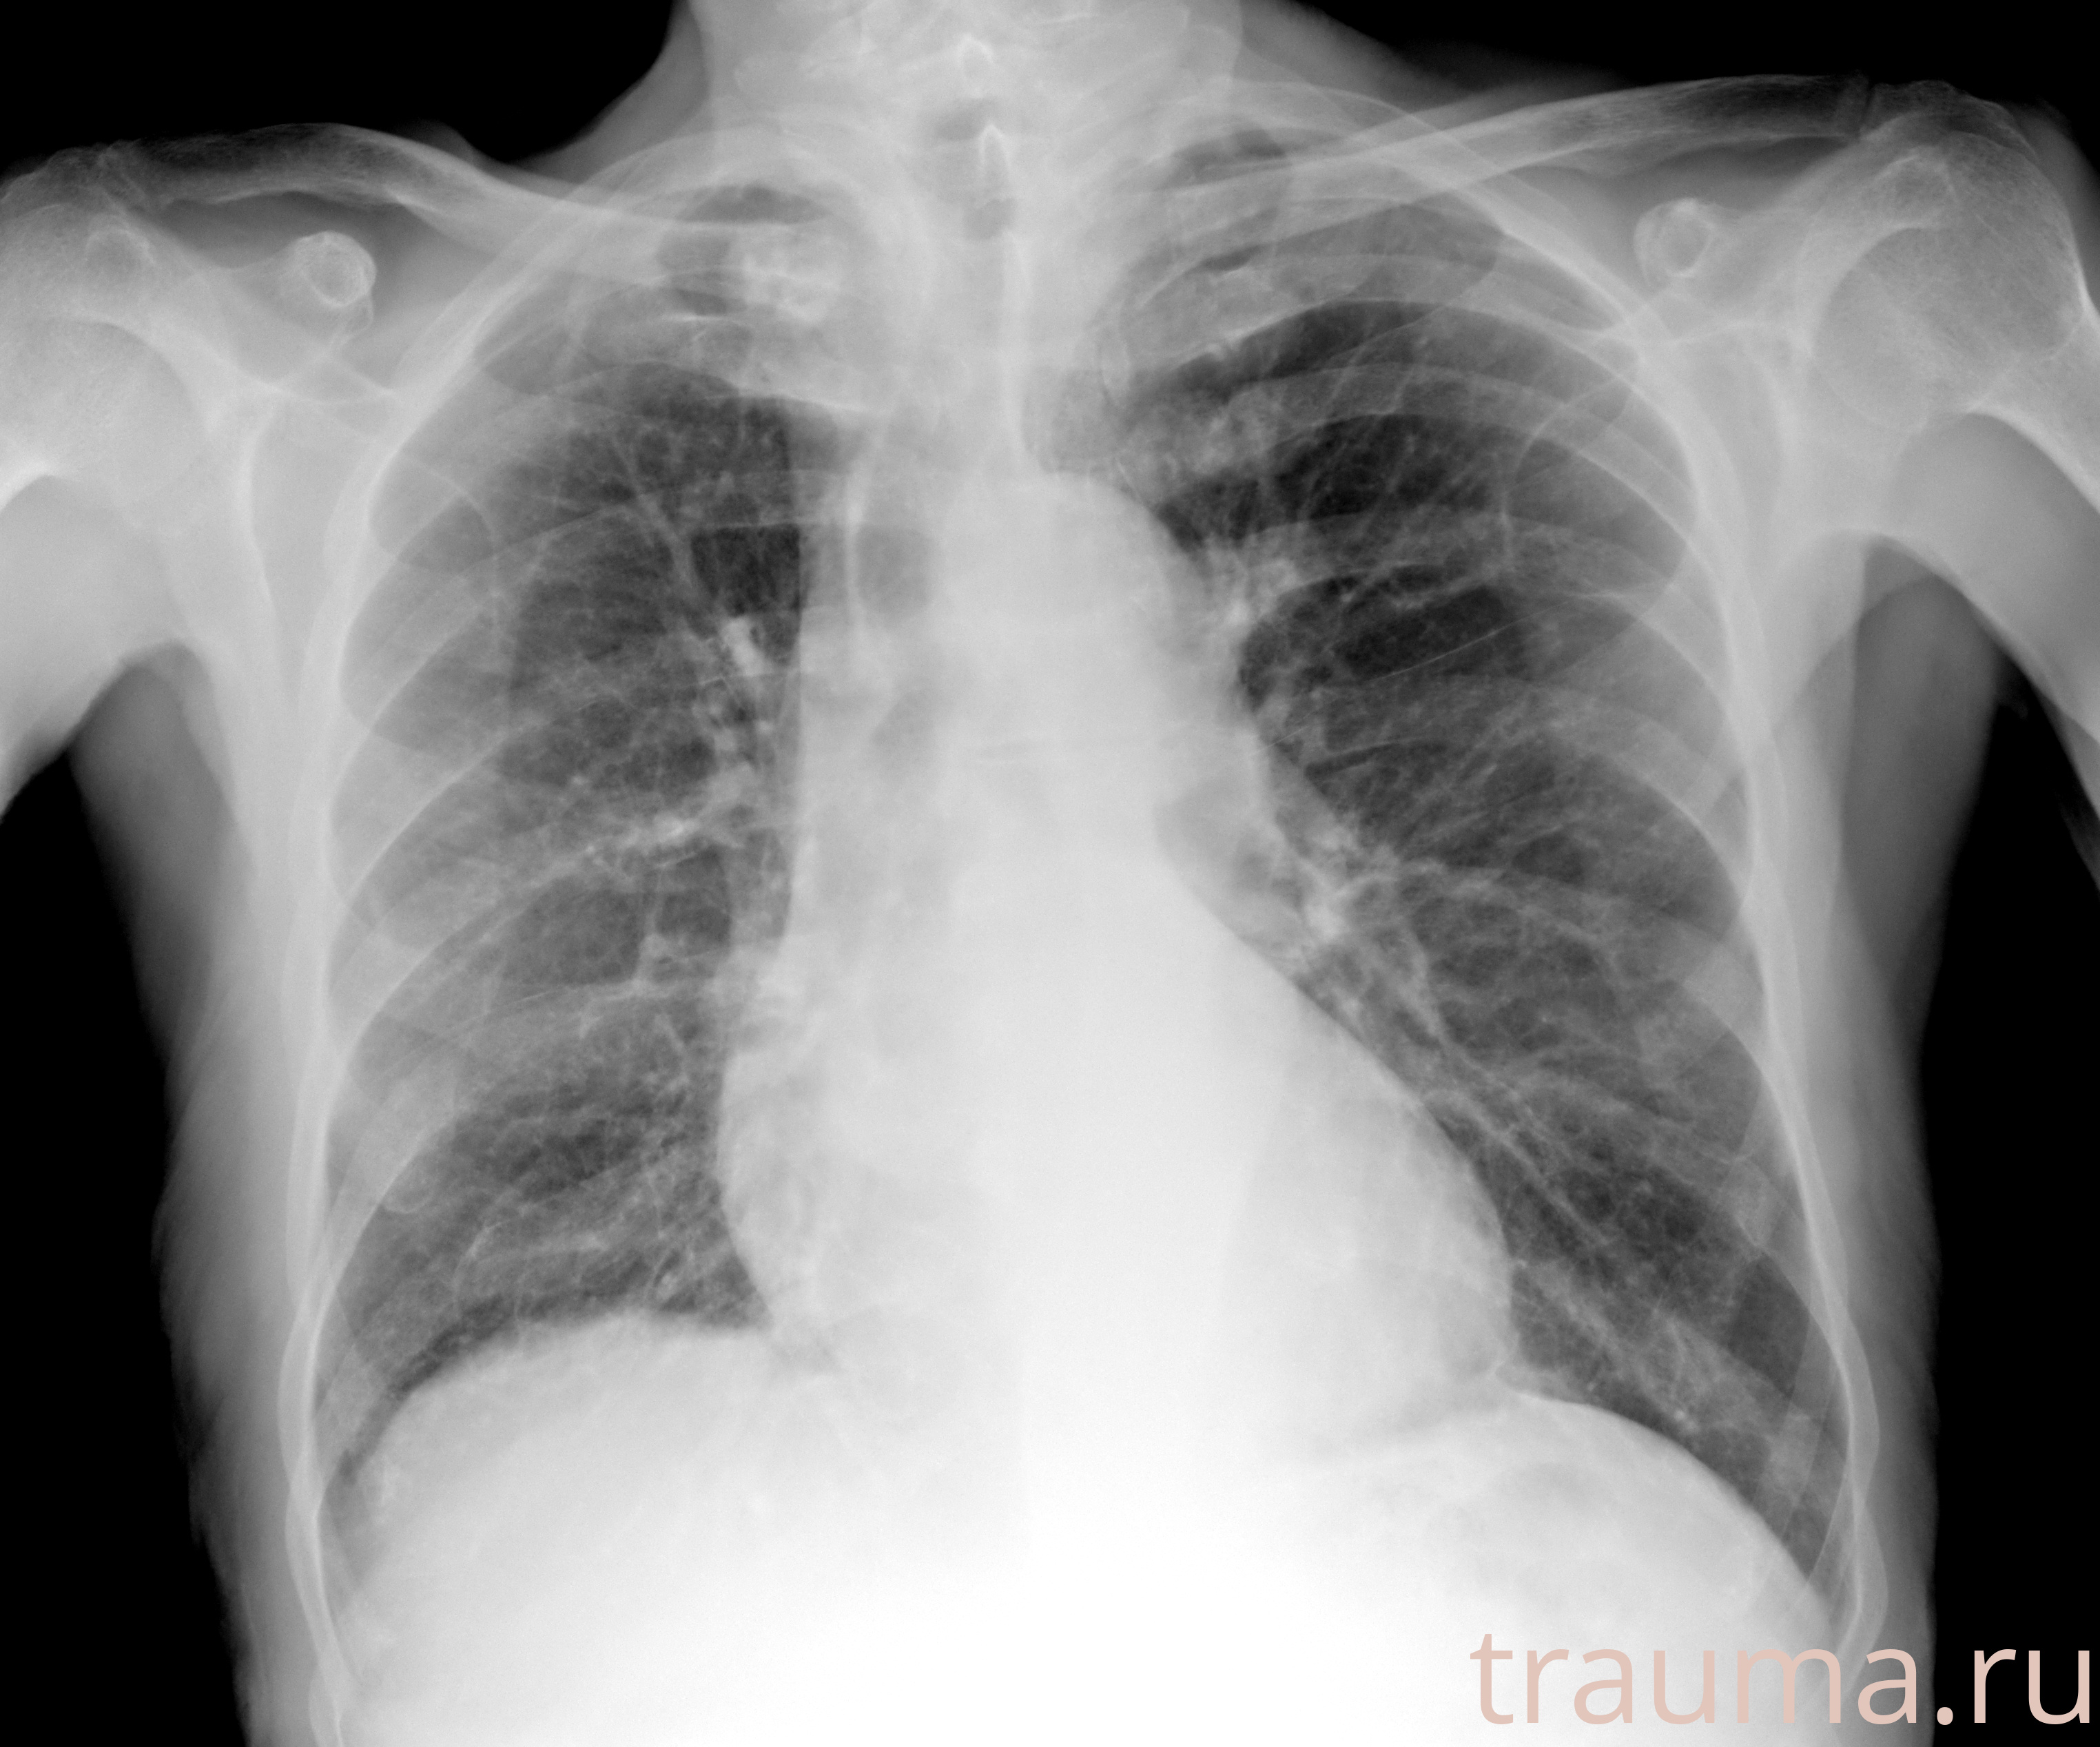

Рентгенограммы

Рентген на дому: по вашему адресу приезжает врач-рентгенолог, травматолог-ортопед с мобильным рентгеновским аппаратом, проводит диагностику травмы или заболевания, делает необходимые рентгенограммы, дает рекомендации по дальнейшему лечению. Получить качественные снимки в домашних условиях возможно благодаря уникальной методике, разработанной МосРентген Центром для института  Склифосовского